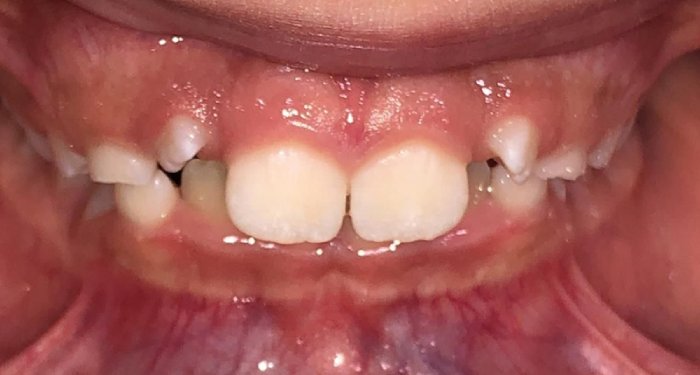

Actual Patient: Victoria

Img Before 1 1 Img After 1 1

Severe Crowding, Narrow Jaws, Severe Deep Bite

image 1 after img

8 months

Front View

Top View

Right & Left Sides